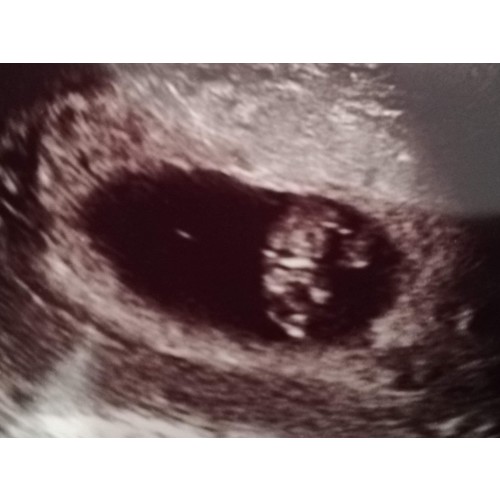

Zo zag de mijne eruit 8+ 4